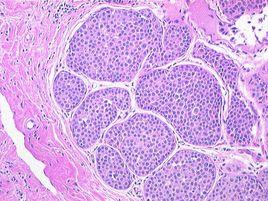

乳腺導管癌導管癌分為兩組微浸潤導管癌和浸潤性導管癌,浸潤性導管癌標準:(1)細胞異型,細胞核增大,濃染,染色質分布不均,核漿比例增大。(2)細胞排列極象紊亂,瘤細胞在導管內形成多種形態的排列方式。(3)癌細胞浸潤周圍間質,癌細胞周圍的纖維間質增生,與癌細胞接觸處出現增生的纖維間質斷裂,Actin免疫組織化學染色癌細胞巢周圍陰性,或者癌細胞巢周圍陽性出現斷裂,不能圍繞癌細胞巢周圍一圈。微浸潤性導管癌標準:滿足前面三條標準,同時滿足有一個或幾個小而清楚的顯微鏡下小灶性浸潤纖維間質。乳腺增生性病變包括纖維腺病、纖維腺瘤、導管乳頭狀瘤病、導管內上皮增生。